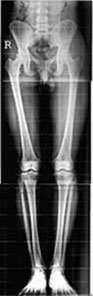

What are Full Length Digital

X-rays?

Full-length radiographs are important radiographs

in orthopedics, where x-rays of the whole spine or

the entire lower limbs are obtained. These are mainly

indicated for measurements of length and angles and

important prior to some types of surgeries.

Why are Full Length X-rays such a big deal?

Traditionally, it has been difficult to obtain full-length

radiographs in our part of the world on a regular

basis - many of us have tried local, ingenious methods

of getting those three or two radiographs and taping

them together.With the digital x-ray technology, we

are now able to "stitch" multiple radiographs

to obtain full-length images, which are then printed

on one film. Two representative examples are given

alongside. |